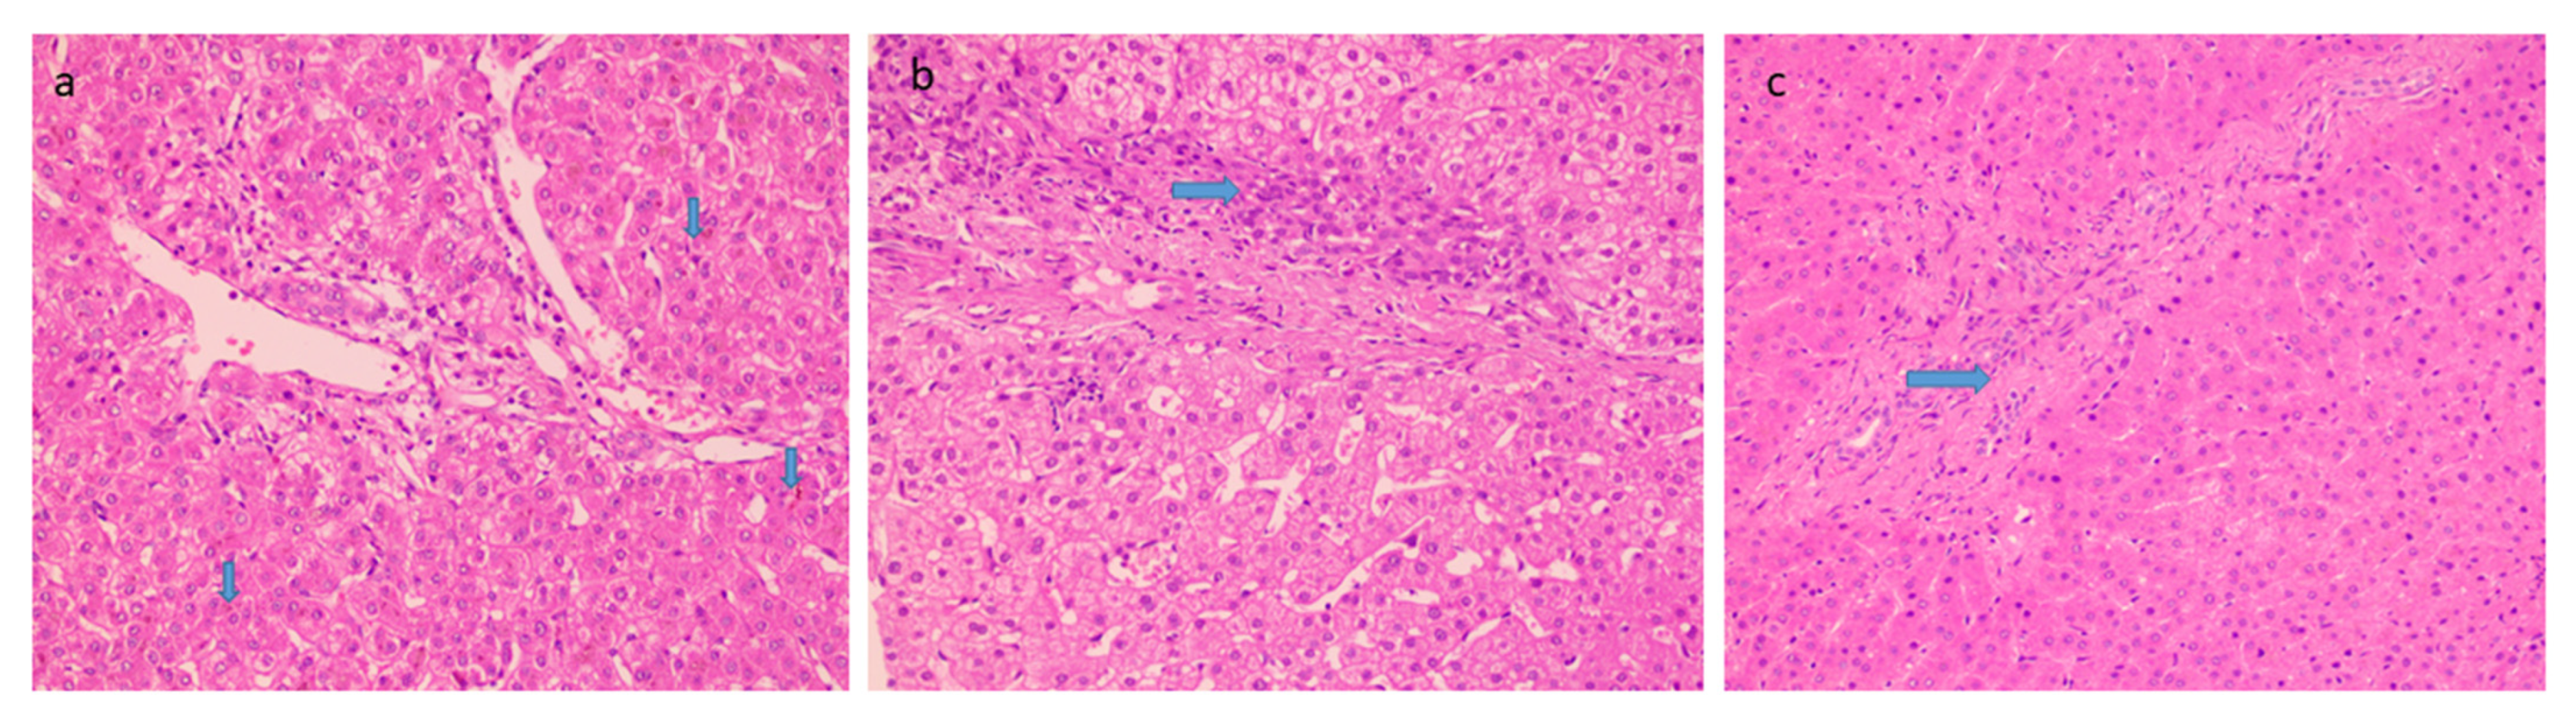

Histological features favoring cholangiopathy were found in less than half of the cases and features were of mild grade- bile ductular reaction in 44% (Figure 3a) whereas reactive biliary changes were noted in only 10% of the cases. Hepatocellular and canalicular bile was found in only 9 cases (18%) (Figure 3b). There was increased periportal and/or zone 3 perisinusoidal fibrosis in 38% (Figure 3c). 12% of patients showed the presence of occasional thin fibrous bridges. Cirrhosis or advanced fibrosis was not seen in any of these cases. One-fourth of the cases (12) showed concomitant minimal to mild hepatocyte steatosis.

Figure 3.

Histological features favoring biliopathy (a) bile stasis (20×, HE, arrow) (b) ductular reaction (20×, HE, arrow) and (c) increased periportal fibrosis (20×, HE, arrow).